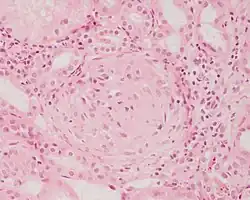

Meningoma | Concentrically calcified basophilic structure in the centre of the field in a meningioma. | Category: Histopathology of meningoma | meningoma |

![]() |